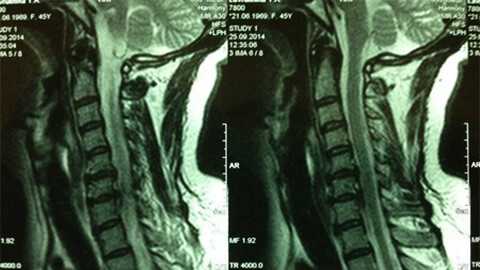

МРТ при грыже межпозвоночного диска и шейного синдрома из-за него

- магнитно-резонансная томография: благодаря высокой степени визуализации, позволяет видеть даже начальные изменения; в настоящее время является основным методом диагностики;